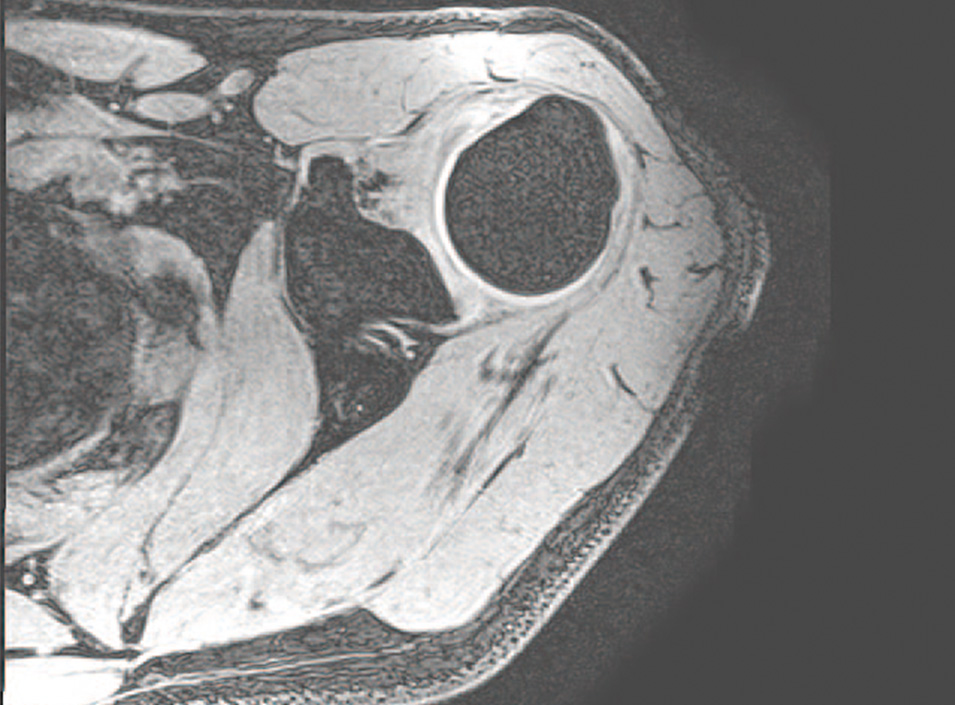

このセミナーをきっかけに始まったのが、「野球ひじ」の早期発見を目的とした画像認識・解析技術の開発です。野球ひじとは、投球動作によって生じるひじの障害のこと。骨や軟骨が未発達な成長期の子どもが発症しやすいとされています。肩甲骨の形や動きを診ることで早期発見が可能ですが、診察には1人につき30分ほどと長めの診察時間を要します。また、診察には一定の経験も必要で、一日に診られる患者の数には限度があります。この課題を解決するため、近藤教授は札幌医科大学の保健医療学部と連携。自身が研究してきたAIを活用した画像解析技術を使い、患者の骨の状態を過去の症例と照合して診断をサポートするツールの開発に取り組みました。「患者の多くが子どもということもあり、現場からは被ばくの少ないMRIを使いたいという要望がありました。しかし骨は水分をほとんど含まないため、磁気共鳴が弱く、MRIの画像では黒く写ってしまい認識がとても難しいのです。さらに骨の周囲も暗く写るため、最初は骨そのものも、骨とそれ以外の境界の判別にも苦労しました。そこから約2年かけて高精度でのMRI画像認識・解析が可能となり、実用化まであと一歩のところまで来ています」と近藤教授は語ります。